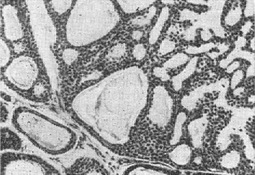

Мікроскопічно цилиндрома має часточкову будову і складається з дрібних базофільних клітин з темними ядрами, що формують залози, трубки, тяжі, криброзные (мережані) структури і солідні ділянки (рис. 1). Характерними для цилиндромы є гомогенні гіалінові або слизоподібні маси, заповнюють розширені залози і трубки і утворюють циліндри, що нагадують білкові циліндри в канальцях нирок, що і послужило підставою для назви пухлини. Зустрічаються також виконані гіаліновими масами великі кістозні порожнини. Мітози в пухлини спостерігаються рідко.

Рис. 1. Цилиндрома м'якого неба.